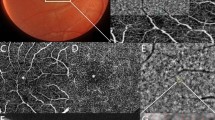

Multimodal imaging in eight patients with achromatopsia showing the spectrum of abnormal near-infrared autofluorescence, and corresponding optical coherence tomography and short-wavelength autofluorescence images. Semiquantitative autofluorescence plots (right) show normalized autofluorescence signals, plotted after segmentation along semi-circles centered on the fovea. The horizontal dimension of the inner segment ellipsoid interruption on optical coherence tomography, if present, is reported as a striped area on autofluorescence plots. In Case #6, a hyperautofluorescent perifoveal ring was barely visible on short-wavelength autofluorescence (white arrowhead) but was clearly visible on the semiquantitative plot, illustrating the interest of this image process to emphasize details in low-quality, noisy images. SD-OCT = spectral domain optical coherence tomography; SW-AF = short-wavelength autofluorescence; NIR-AF = near-infrared autofluorescence; yo = year old; M = male; F = female.

On SW-AF, the most frequent abnormal feature was a pathognomonic perifoveal hyperautofluorescent ring, that was observed in n = 12 subjects (75%). The semiquantitative autofluorescence plots contributed to identify this ring in a low-quality autofluorescence acquisition due to photophobia, nystagmus and poor fixation (Case #6, Fig. 1). The four cases without perifoveal hyperautofluorescent ring on SW-AF had an abnormal foveal SW-AF profile, consisting in an enlarged (Case #5, Supplementary Figure 1) or a steep central SW-AF depression (Cases #1, Fig. 1; #2 and #12, Fig. 2).

On NIR-AF, the usual increased autofluorescence was present at the center of the macula in all eyes, with a variable signal strength ranging from very faint (Case #9, #11, Fig. 2) to intense (Case #13, #14, Fig. 1; and #8, Fig. 2). Within the macular hyperautofluorescent area, the most frequent abnormal feature of NIR-AF was a central hypoautofluorescent spot of variable size, that was observed in n = 7 subjects (44%), all displayed in Fig. 1. This central hypoautofluorescence, visible on the NIR-AF images, was confirmed by the semiquantitative NIR-AF plots, where it appeared as a central depression whose lowest value reached below the values of the control curve. Among those subjects, two presented in addition a perifoveal NIR-AF hyperautofluorescent ring, colocalizing with the border of the hypoautofluorescent area, as demonstrated by the sharp demarcation visible on semiquantitative autofluorescence plots (Cases #10 and #13, Fig. 1). The remaining cases that did not harbor a central hypoautofluorescent area on NIR-AF are displayed in Fig. 2 (normal appearance of the NIR-AF, n = 7) and in the Supplemental Figure 1 cases, #5 and #7, with borderline NIR-AF plots displaying an ill-defined central decrease in NIR-AF, that could not be clearly categorized into either group). Noticeably, a discrete foveal hyperautofluorescent spot was observed in n = 3 cases (Case #8, #11 and #15, Fig. 2) on the NIR-AF plots.